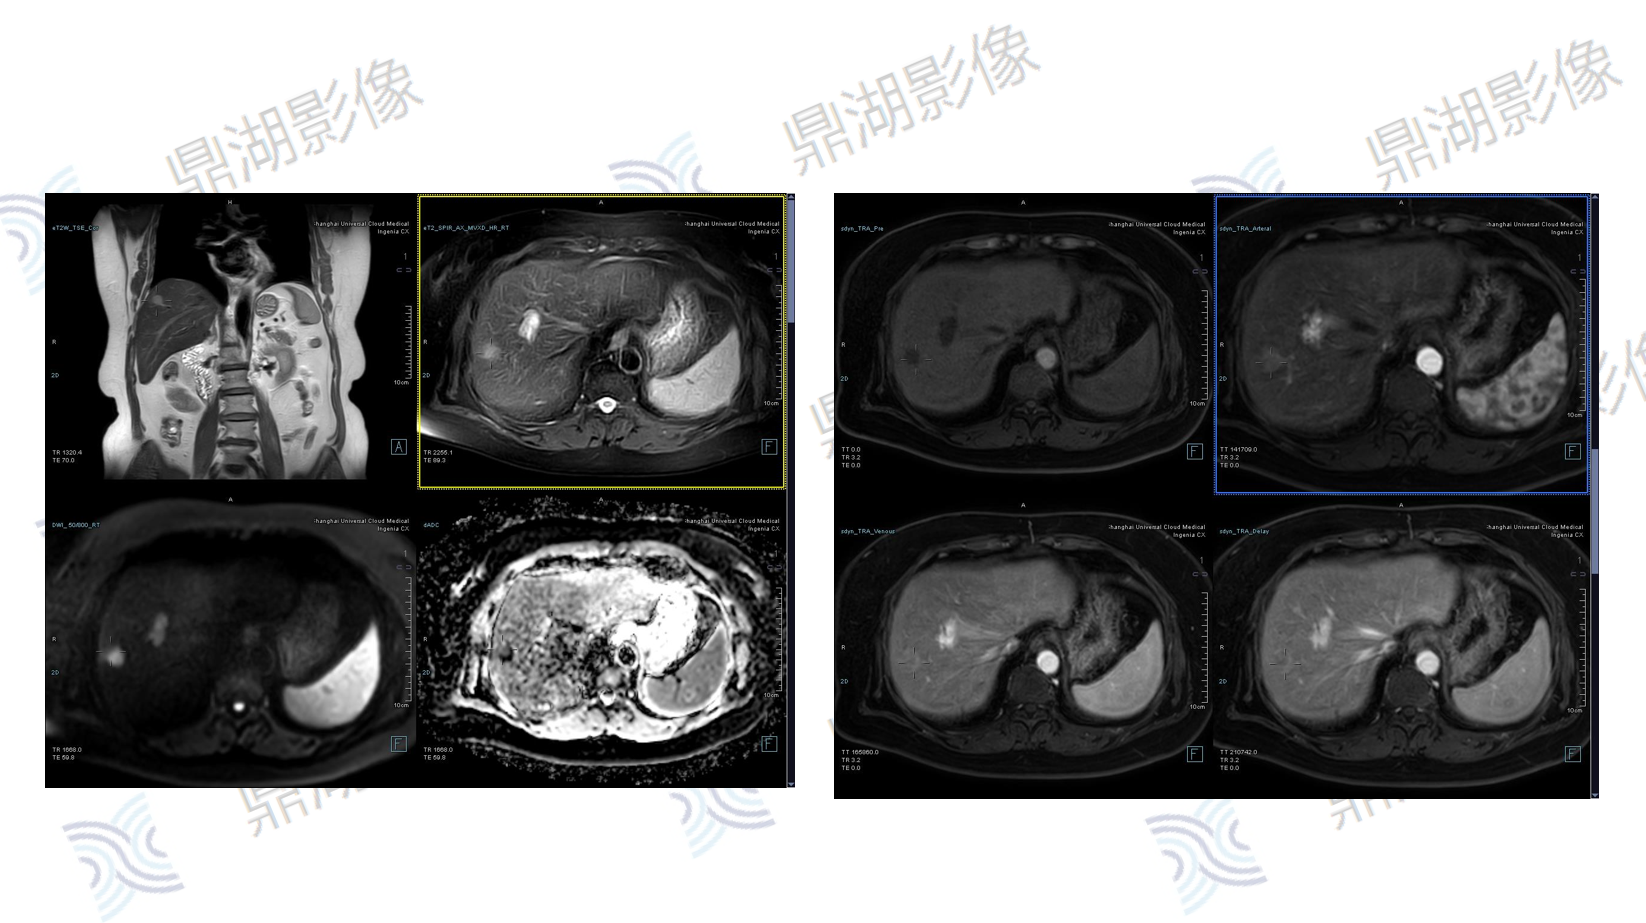

主诉:B超肝实质回声细密增强,MRI提示肝左外叶结节,考虑恶性可能